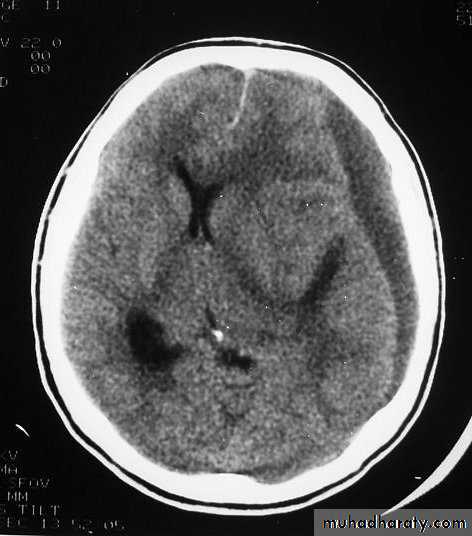

They can increase both brain metabolism and blood flow, therefore increasing intracranial pressure.5. Hydrocephalus

a. Acutely due to obstruction of CSF outflow due to intraventricular blood.b. Delayed post-traumatic communicating hydrocephalus due to impaired CSF reabsorption following traumatic subarachnoid haemorrhage

Intraventricular blood can lead to Hydrocephalus